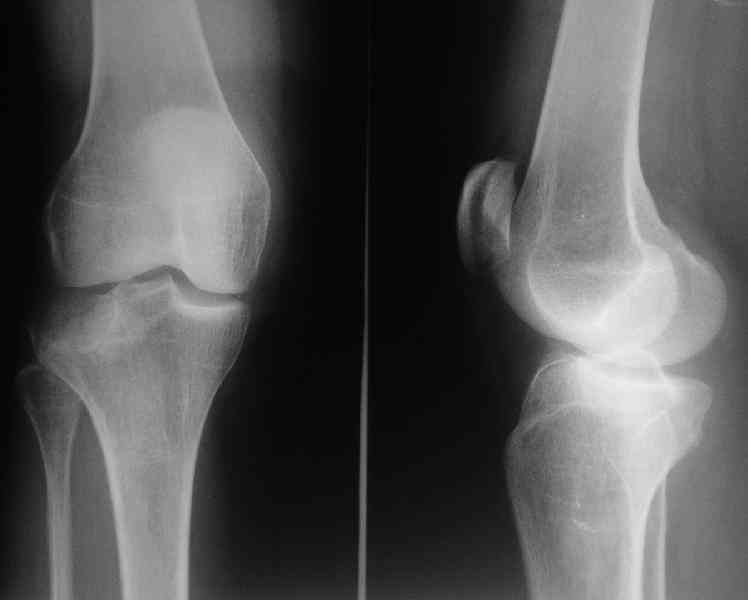

Здравствуйте, уважаемые коллеги!Подскажите, пожалуйста, какой выбрать доступ и способ фиксации при импрессионном переломе заднего отдела наружного мыщелка большеберцовой кости. Женщина 40 лет, травму получила 02.01.2008, катаясь на горных лыжах.Есть ли здесь необходимость использовать задний доступ, или можно справиться через наружный? Есть ли шансы сделать закрыто - под ЭОП через медиальное "окошко" поднять забойником суставную поврехность? Какой лучше использовать фиксатор?Спасибо.

центральная импрессия, а при ипрессии с краевым переломом - после приподнимания импрессии опорная (Butress) пластина, как на снимке.

In this situation, where the fragment is posterolateral, one needs a posterior approach, either as described by Timothy Bhatacharya et al in 2005 in JOT, which involves taking down the medial head of the gastrocnemius, or the Lobenhoffer paper which involves a transfibular approach.